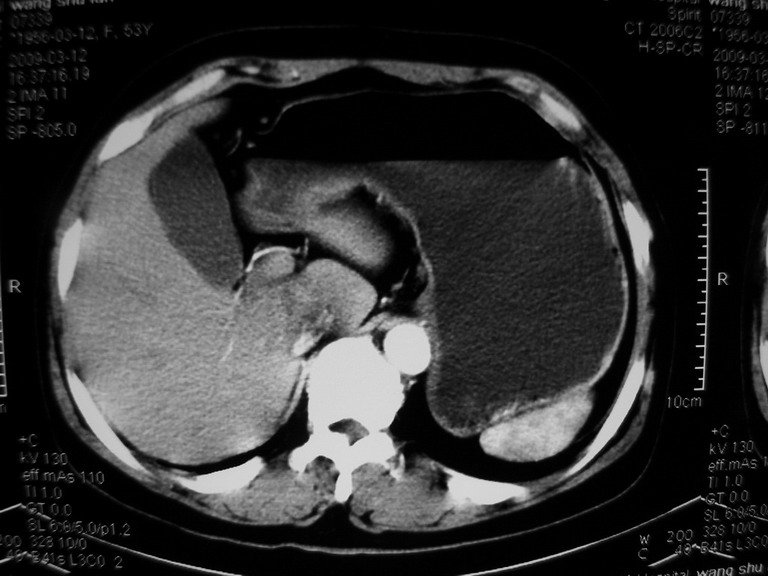

患者,女性50岁,上腹部不适2年余,既往多次腹部彩超未见异常,今日上午在我院查彩超发现肝右叶囊实性病变,外院辅助检查,afp,cea,ca199, 都在正常范围内,无肝炎史否认肿瘤史,生活在牧区

接着往下一贴看,有静脉期和延迟期,在看看和下腔静脉及十二指肠的关系,腔静脉内是不是栓子?

考虑肝右叶与尾叶交界区肝癌(部分外生),侵犯下腔静脉并下腔静脉瘤栓形成。

肝包虫病可能性大